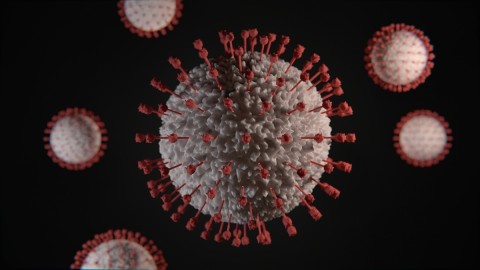

Novi soj koronavirusa "Frankenštajn" dominantan u Evropi, bez težih simptoma

Novi soj koronavirusa, označen kao XFG i nazvan "Frankenštajn", postao je dominantan u Evropi, a prema podacima Evropskog centra za prevenciju i kontrolu bolesti (ECDC), ovaj soj činio je početkom septembra...